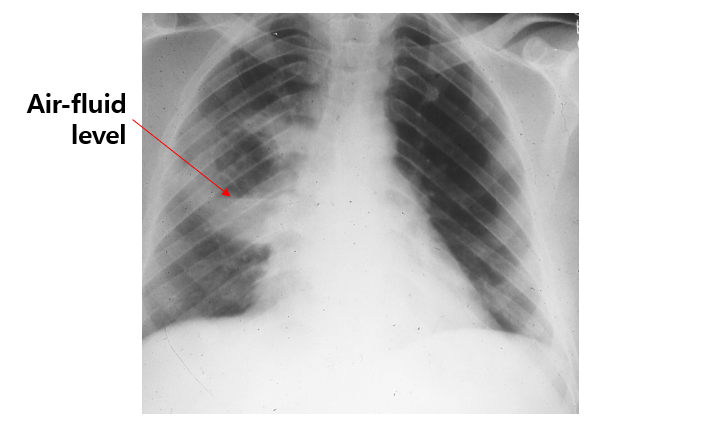

흡인 가능성을 시사하는 병력과 함께 CXR에서 air-fluid level이 있는 공동이 보일 때 1차성 폐농양을 진단할 수 있음을 알고, 그에 따른 경험적 항생제인 clindamycin, beta-lactam 등을 알면 충분하다.

2) CXR: Air-fluid level이 보이는 두꺼운 벽의 공동(thick-walled cavity)